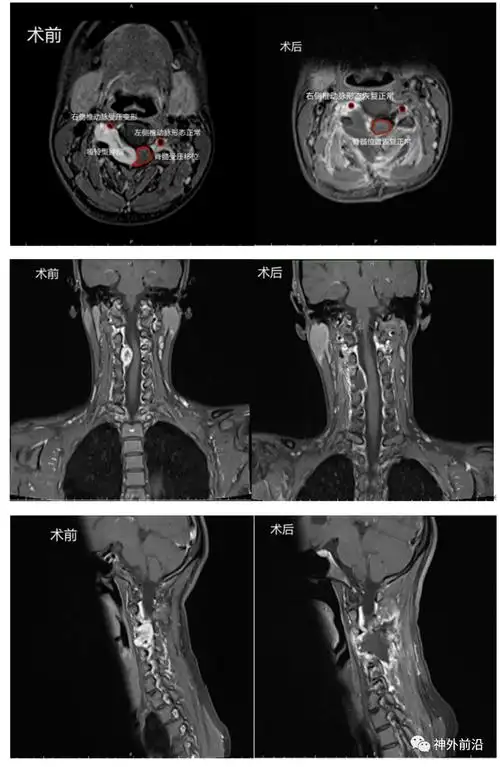

内镜前沿内镜手术切除高位颈髓哑铃型肿瘤同时减少骨质破坏一例世纪坛